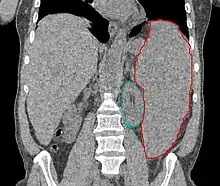

![]() | |

| Blood smear from a person with myelodysplastic syndrome. A hypogranular neutrophil with a pseudo-Pelger-Huet nucleus is shown. There are also abnormally shaped red blood cells, in part related to removal of the spleen. | |